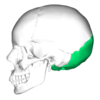

1

Q

A

frontal bone